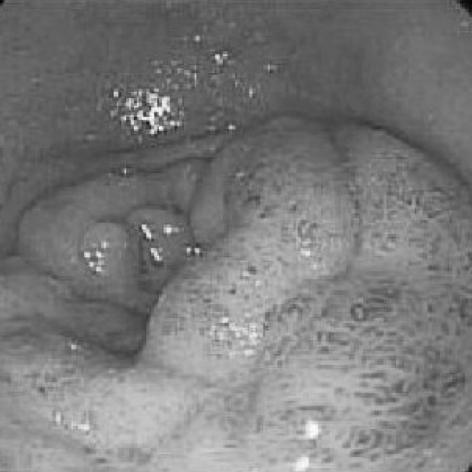

Brunner's gland hyperplasia is a benign tumor of the duodenum and it is rarely associated with clinical symptoms. We report on a 64-yr-old man with Brunner's gland hyperplasia who had undergone a duodenocephalo-pancreatectomy. The reason is that he presented upper gastrointestinal obstructive symptoms and the esophagogastroduodenoscopic finding revealed the lesion to be an infiltrating type mass on the second portion of the duodenum with luminal narrowing. An abdominal computed tomography showed a 2.5 cm-sized mass in the duodenal second portion with a suspicious pancreatic invasion and 7 mm-sized lymph node around the duodenum. Duodenocephalopancreatectomy was successfully performed. Histological examination revealed a Brunner's gland hyperplasia. The final diagnosis was the coexistence of Brunner's gland hyperplasia and pancreatic heterotopia with a pancreatic head invasion. The literature on Brunner's gland hyperplasia is reviewed.

布伦纳腺增生是十二指肠的一种良性肿瘤,很少伴有临床症状。我们报告一例64岁患有布伦纳腺增生的男性患者,其接受了十二指肠胰头切除术。原因是他出现了上消化道梗阻症状,食管胃十二指肠镜检查发现病变为十二指肠第二部的浸润型肿物,管腔狭窄。腹部计算机断层扫描显示十二指肠第二部有一个2.5厘米大小的肿物,怀疑有胰腺侵犯,十二指肠周围有一个7毫米大小的淋巴结。成功实施了十二指肠胰头切除术。组织学检查显示为布伦纳腺增生。最终诊断为布伦纳腺增生与胰腺异位并存,并侵犯胰头。本文对布伦纳腺增生的相关文献进行了综述。